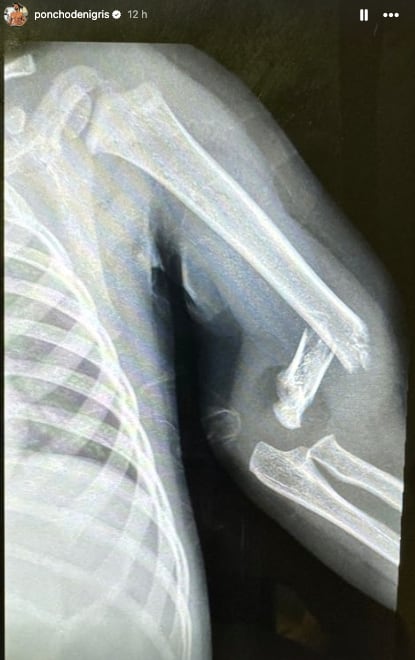

Para evitar amarillismo y malos entendidos, Poncho de Nigris mostró la radiografía que muestra que a Toñito se le rompió el brazo izquierdo.

Al levantarlo, Poncho de Nigris notó que Toñito tenía flojo el brazo y que además le tronaba por lo que decidió llevarlo de inmediato al hospital, donde le dijeron que estaba roto.

El niño fue programado a cirugía por lo que a las 21 horas del día miércoles 10 de julio lo operaron para colocarle clavos, intervención que, de acuerdo con el influencer, era de bajo riesgo.